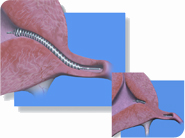

ESSURE® is a fallopian tube occlusion device. It is a small insert that the doctor positions into the first segment of your fallopian tubes through the natural pathways. The inserts conform to the shape of the tube and over 3 months (approximately) progressively form a complete barrier preventing sperm from reaching the egg (gametes cannot fuse).

Using the hysteroscopy procedure, the gynecologist positions soft and flexible micro-implants (micro-inserts) via the body’s natural pathways (navigating through the vagina and cervix and up to the uterus) in the first segment of the fallopian tubes.

These inserts are a type of stent made from a stainless steel alloy (with Nitinol™, a metal alloy of nickel and titanium, which raises the question whether women with nickel allergies would suffer adverse reactions) and the centre of the stent contains Polyethylene terephthalate (PET). PET provokes an inflammation response which produces fibrosis and blocks the fallopian tube. The ESSURE® method can be carried out in a clinic or a hospital usually on an outpatient basis and without general anesthesia. No incisions are needed and so there is no scarring. Most women can expect to go home on the day of the Essure® procedure and return to normal activities the same day or in the days immediately following the procedure.

- A hysteroscope is delicately inserted into the uterus and the proximal tubal opening is sighted. The micro-implants (Essure®) are loaded into the hysteroscope and placed (they are slid into the tubes and then put into position) into each fallopian tube.